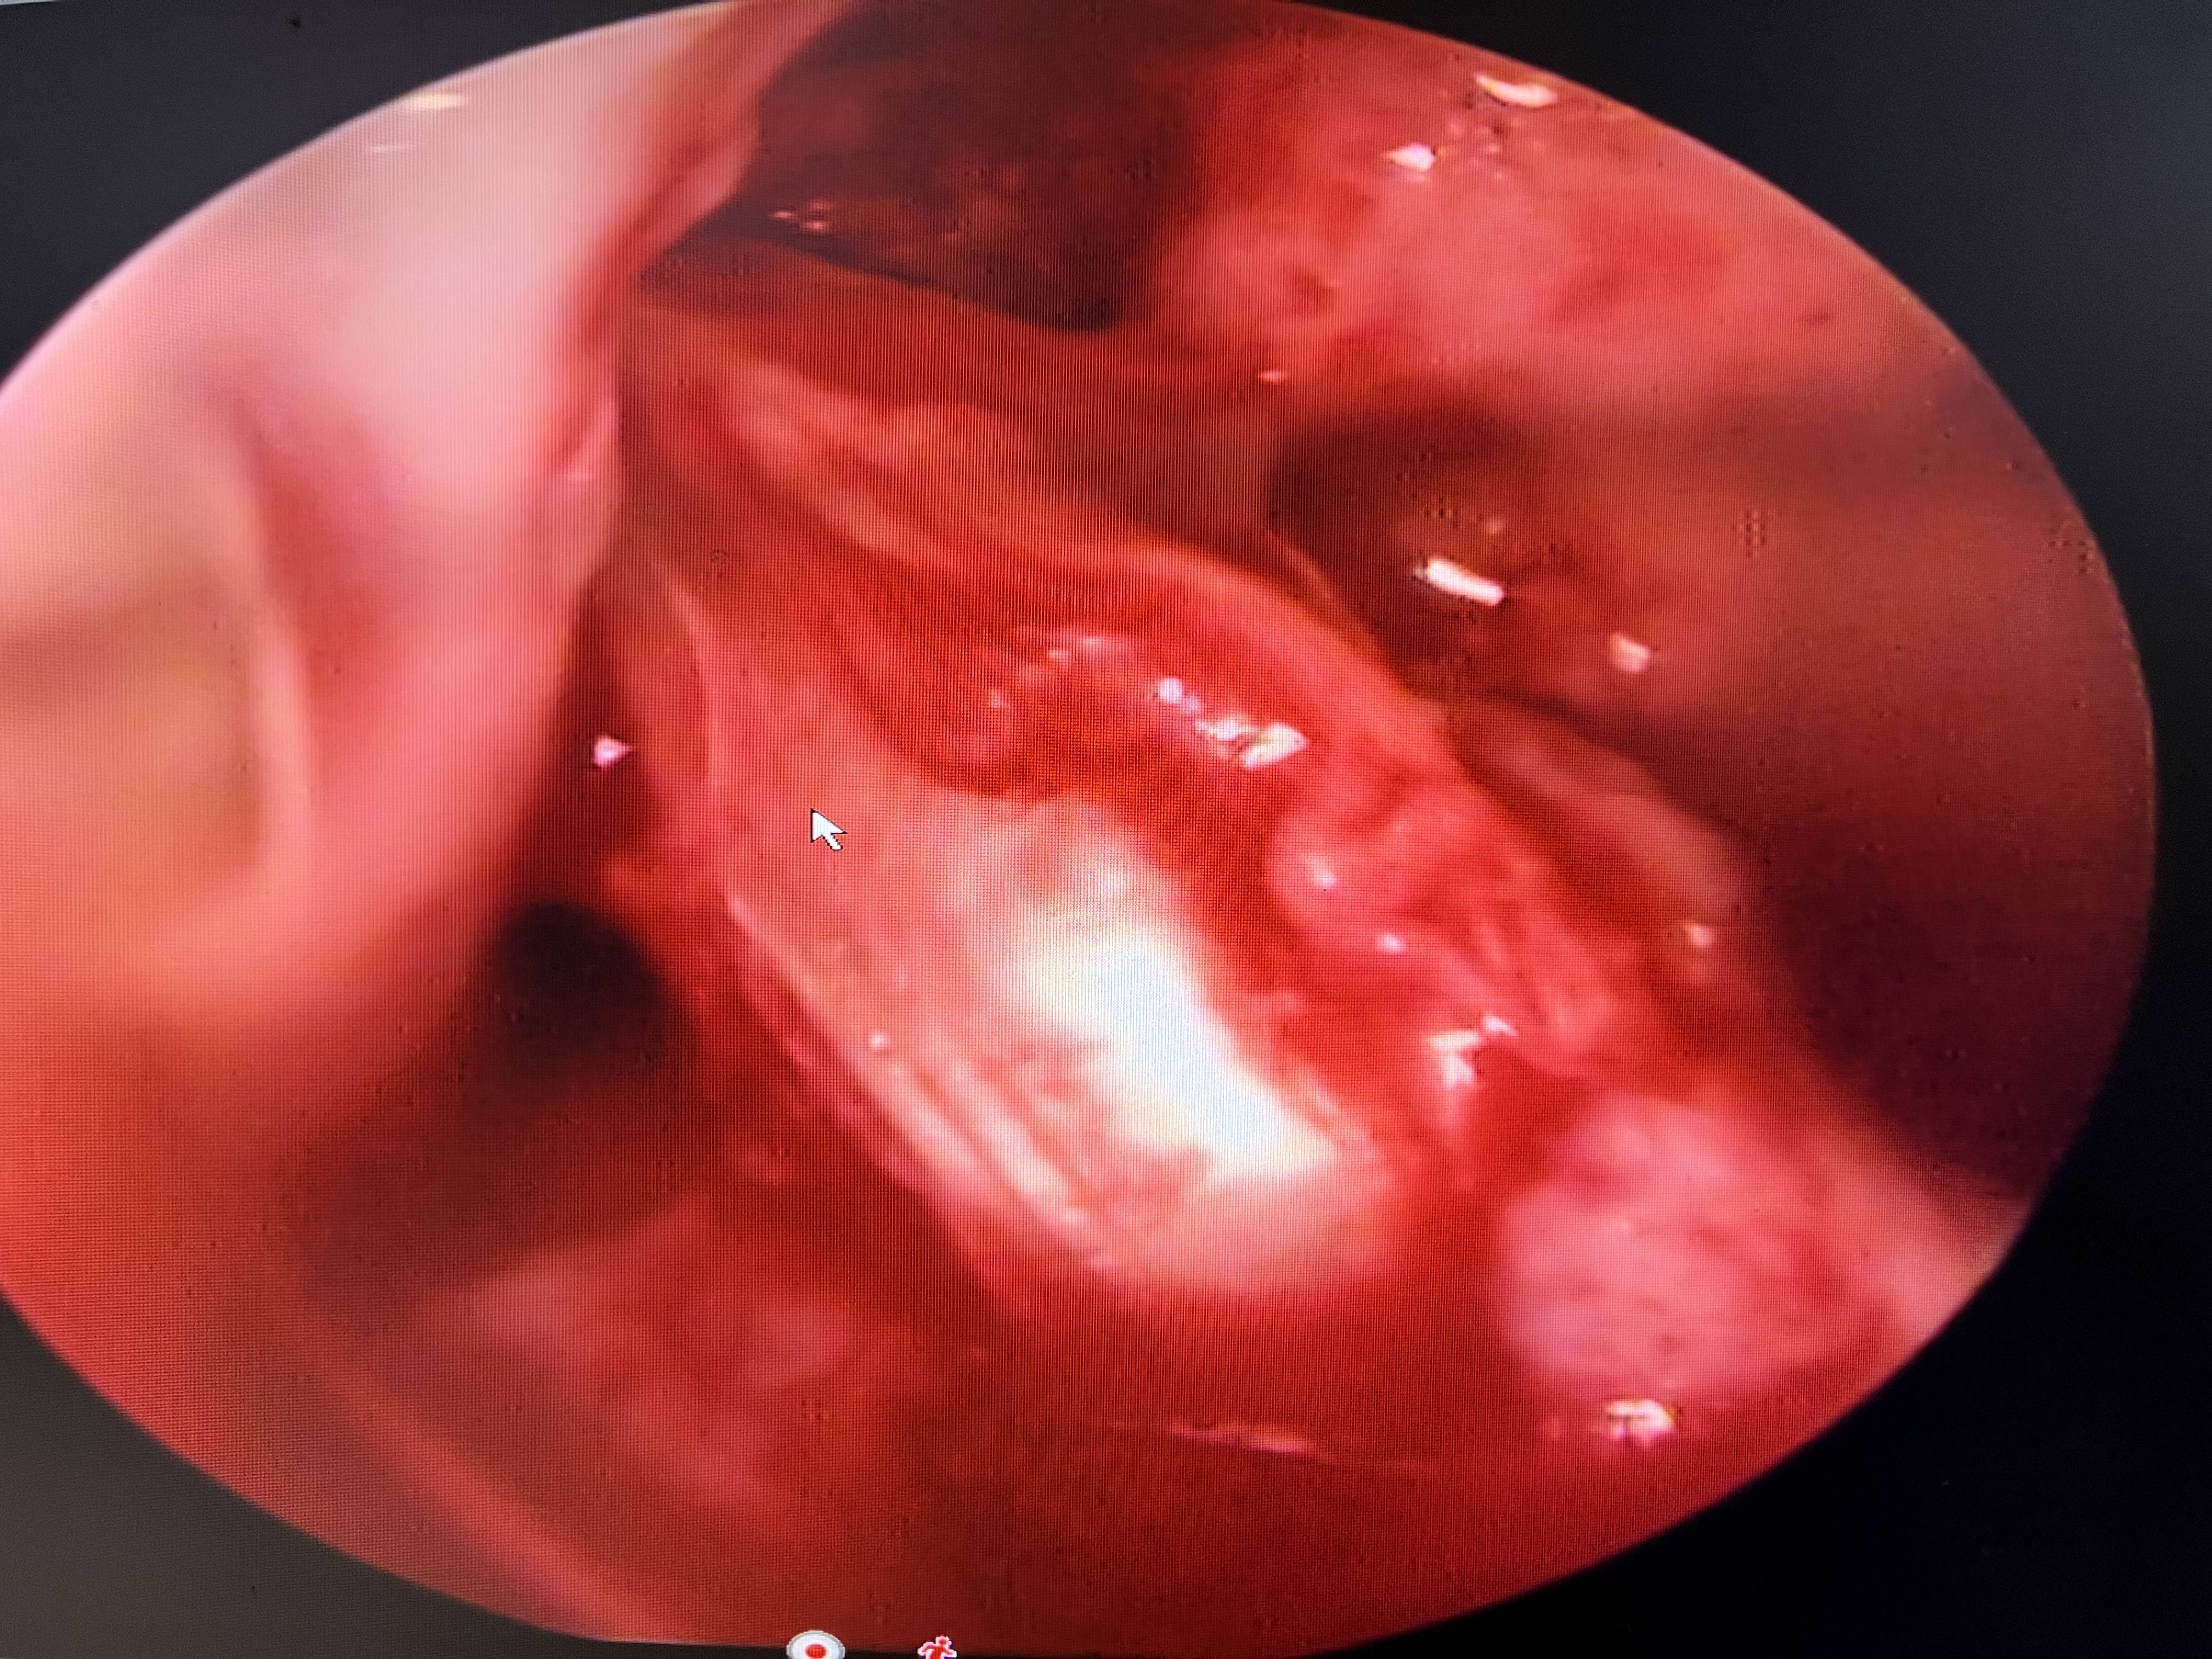

Shoulder dislocation ka treatment Dr Naveen sharma ke paas available hai.  isme sabse pahle three tesla wala mri karwana hota hai. jisse pata chal jata hai ki aapke bone loss kitna hai ya hil sach kitna hai ya bankart kitna h

iske hisab se aage ka treatment kiya jata hai jisme yadi bone loss jyada ho to latarjet surgery kanra sahee rahega aur yadi aapko high demand ho to bhe elatarjet accha rahata hai

yadi aapo jyada heavy kaam jaise gym nahee karna hai ti fir aap arthroscopy bnkart repair bhe ekarwa sakte ho jisme suture anchor se bankart ko repair kiya jata hai.